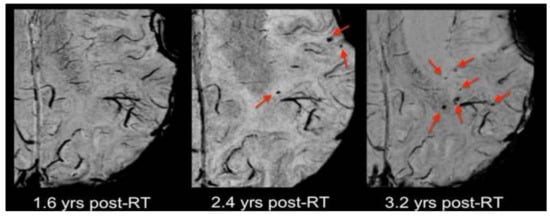

- Tanyildizi, Y.; Keweloh, S.; Neu, M.A.; Russo, A.; Wingerter, A.; Weyer-Elberich, V.; Stockinger, M.; Schmidberger, H.; Brockmann, M.A.; Faber, J. Radiation-induced vascular changes in the intracranial irradiation field in medulloblastoma survivors: An MRI study. Radiother. Oncol. 2019, 136, 50–55. [Google Scholar] [CrossRef]

- Lupo, J.M.; Chuang, C.F.; Chang, S.M.; Barani, I.J.; Jimenez, B.; Hess, C.P.; Nelson, S.J. 7-Tesla susceptibility-weighted imaging to assess the effects of radiotherapy on normal-appearing brain in patients with glioma. Int. J. Radiat. Oncol. Biol. Phys. 2012, 82, e493–e500. [Google Scholar] [CrossRef]

- Lupo, J.M.; Molinaro, A.M.; Essock-Burns, E.; Butowski, N.; Chang, S.M.; Cha, S.; Nelson, S.J. The effects of anti-angiogenic therapy on the formation of radiation-induced microbleeds in normal brain tissue of patients with glioma. Neuro Oncol. 2016, 18, 87–95. [Google Scholar] [CrossRef]

- Peters, S.; Pahl, R.; Claviez, A.; Jansen, O. Detection of irreversible changes in susceptibility-weighted images after whole-brain irradiation of children. Neuroradiology 2013, 55, 853–859. [Google Scholar] [CrossRef]